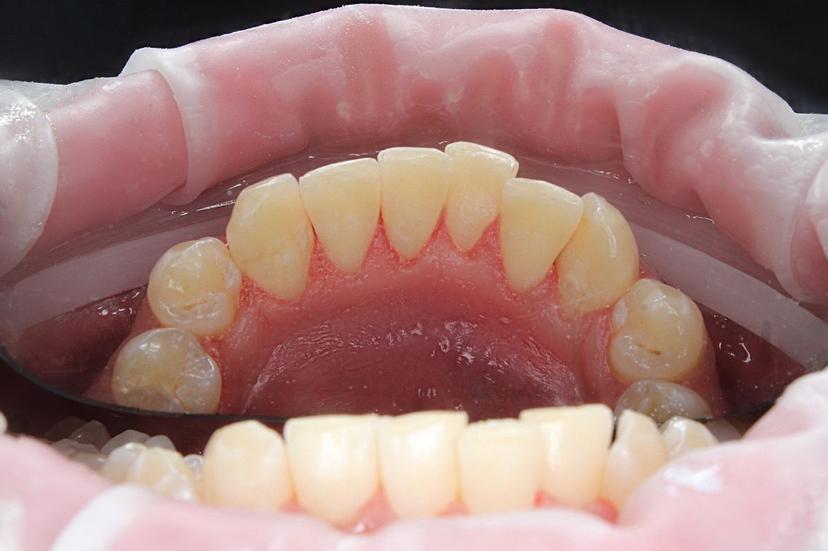

Пигментированный зубной налёт "Присли" у пациента 11 лет.

Профессиональная гигиена проводилась при помощи аппарата Air Flow, позволяющего удалить зубной налёт. Завершающим этапом было полирование зубов, которое позволяет сократить дальнейшее образование налёта.